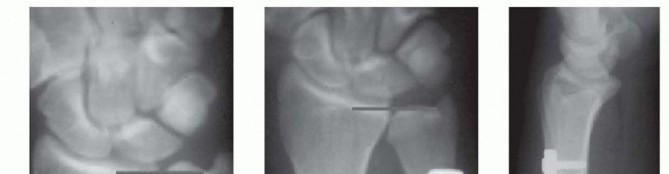

Imaging serves as our architectural blueprint for surgical planning. We mandate a comprehensive plain radiographic series. This begins with strictly neutral rotation posteroanterior (PA) and lateral views of both wrists to accurately assess static ulnar variance and the morphology of the sigmoid notch. However, static views are insufficient. We must obtain a pronated grip view (the clenched fist PA). As Tomaino and others have definitively demonstrated, active power grip forces the radius proximally relative to the ulna, increasing dynamic ulnar variance by an average of 2.5 mm. This view often unmasks profound dynamic impaction in wrists that appear neutrally variant on resting films.

Advanced imaging and diagnostic modalities are frequently employed to refine our surgical strategy. High-resolution Magnetic Resonance Imaging (MRI), particularly when enhanced with intra-articular contrast (MR arthrography), is invaluable. It allows us to detect central TFCC perforations, evaluate the integrity of the intrinsic carpal ligaments (scapholunate and lunotriquetral), and identify early subchondral cystic changes or bone marrow edema in the proximal ulnar aspect of the lunate—the hallmark of advanced impaction. When diagnostic uncertainty persists, or when concomitant intra-articular pathology requires debridement, we utilize wrist arthroscopy. Arthroscopy remains the gold standard for directly visualizing chondral damage, assessing the trampoline effect of the TFCC, and confirming the precise Palmer classification prior to executing the extra-articular osteotomy.